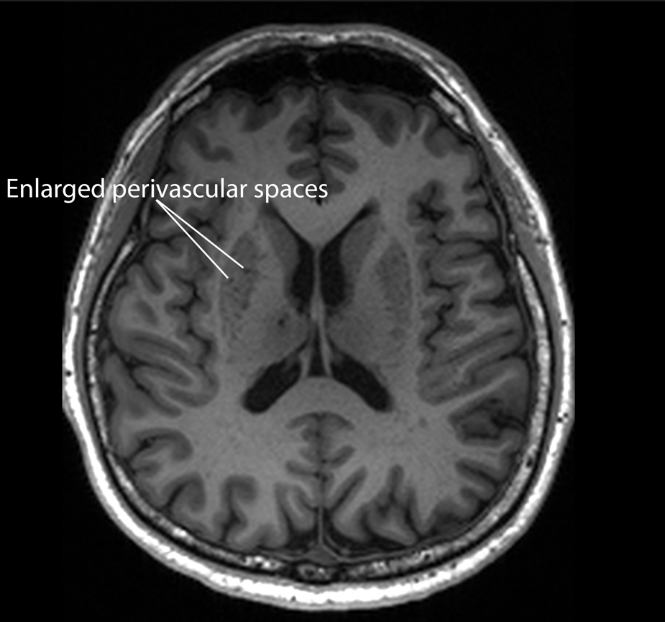

These blocked brain drains, known as enlarged perivascular spaces, seem to act as an early warning sign for Alzheimer’s, which is the most common type of dementia.

Associate Professor Nagaendran Kandiah from NTU’s Lee Kong Chian School of Medicine (LKCMedicine), who led the study, explained that these changes can be picked up on routine MRI (magnetic resonance imaging) brain scans used to investigate memory or thinking problems. Because of this, spotting enlarged perivascular spaces could support current methods of detecting Alzheimer’s at an earlier stage, without needing extra tests that cost more time and money.

Blood vessels in the brain sit within small fluid-filled gaps called perivascular spaces. These spaces act like channels that allow toxic waste products to drain away. These waste products include beta amyloid and tau proteins, which build up in large amounts in the brains of people with Alzheimer’s disease.

When this waste clearance system does not work properly, the perivascular spaces can become clogged and enlarge. These enlarged perivascular spaces are visible on MRI scans. Until now, it was not clear how strongly this condition was linked to dementia, especially Alzheimer’s disease.

The NTU team set out to improve on earlier studies by comparing these blocked brain drains with a wider set of biological signs of Alzheimer’s. They examined how enlarged perivascular spaces matched up with key Alzheimer’s markers, such as beta amyloid protein build-up and damage to the brain’s white matter. White matter is the network of nerve fibres that connects different brain regions and helps them communicate.

For this study, the team reviewed MRI scans from all participants. They found that people with mild cognitive impairment were more likely to have enlarged perivascular spaces, in other words, clogged brain drains, compared with those who had no cognitive problems.

When they compared white matter damage with enlarged perivascular spaces, they found that, in people with mild cognitive impairment, the link between the blood markers and enlarged perivascular spaces was even stronger than with white matter damage. This pattern suggests that clogged brain drains may show up earlier in the disease process than white matter damage.

Assoc Prof Kandiah said the results have “substantial clinical implications”. White matter changes are currently more widely used to assess dementia because doctors can spot them easily on MRI scans. However, the study suggests that enlarged perivascular spaces may offer unique value in identifying early signs of Alzheimer’s disease.